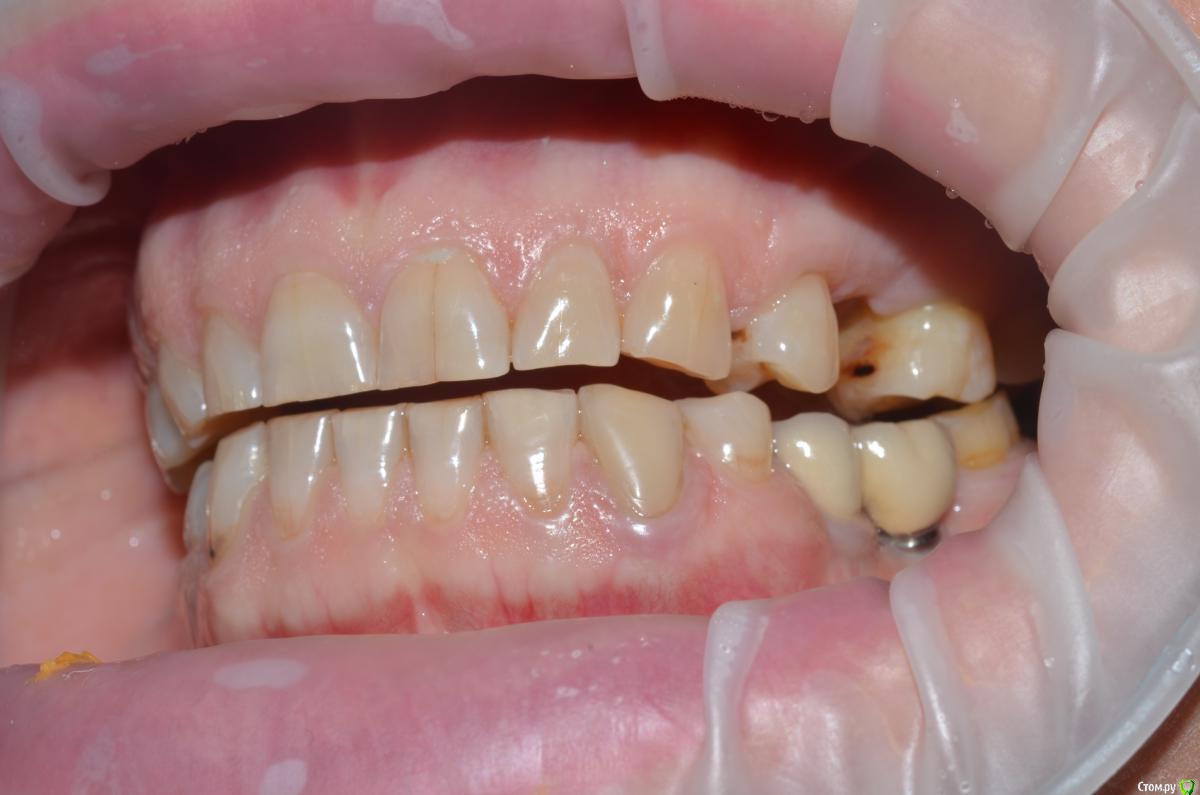

NazranDantist Опубликовано 4 сентября, 2015 Автор Поделиться Опубликовано 4 сентября, 2015 Продолжение кейса. Работа еще не закончена, зуб 25, 35, 36 - аббатменты на подходе, поэтому решили сделать после отпуска пациентки. Фото протокол не соблюдал, курс рубля прыгал, торопился в обменник . Вся работа - имакс на Цереке с редуцированием, фиксация - фронт на чойс, боковые - У-200. Ссылка на комментарий

CHEREDNICHENCO Опубликовано 12 сентября, 2015 Поделиться Опубликовано 12 сентября, 2015 Режет глаз смещение цл, оптг необходимо определенно, хотя бы для оценки состояния тттз и периапикальных тканей в 4 секторе.... Индикатор кариеса используете в работе???.... А зачем в 3 секторе оставили временную конструкцию?! Или это постоянная???..... В десятых- эстетически не вяжется соотношение нижних к верхним... PS: В связи с определенным географическим положением, КНДР находиться в 1 км. 44 м. от места моей работы! и хочу сообщить Вам,- уровень их работ растет от из года, в год! Ссылка на комментарий

CHEREDNICHENCO Опубликовано 12 сентября, 2015 Поделиться Опубликовано 12 сентября, 2015 До протезирования, без смещения! 1.5, 1.6 кариес II класс, 4.3 - V. Как сагиттальную окклюзионную кривую выводили??? Не проще было подождать подхода аббатов...со времянками? Ссылка на комментарий

CHEREDNICHENCO Опубликовано 13 сентября, 2015 Поделиться Опубликовано 13 сентября, 2015 Кариеса нет.DSC_0643.JPGСмещение естьПо фото, когда зубные ряды находятся в контакте- смещение есть! Но на первых фото, когда НЧ находиться в состоянии относительного физиологического покоя, смещения нет! ТО делаю вывод, смещение возникает в результате неправильного соотношения жевательных поверхностей зубов. Ссылка на комментарий